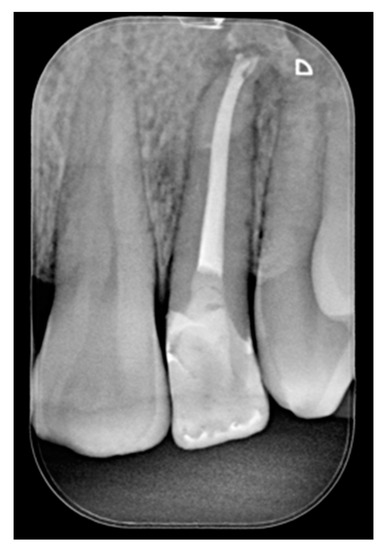

A 42-year old woman presented to the clinic with esthetic concerns related to her upper left lateral incisor (Figure 20). Pre-operative x-rays showed periapical lesion that required retreatment. After retreatment (Figure 21) a treatment plan was proposed to the patient. The ideal treatment would have involved an orthodontic therapy to gain back lost space in mesial portion. The patient decided not to consider an orthodontic treatment and accepted just the restorative proposal (Class IV restoration). Considered the sufficient amount of ferrule no post was applied [16]. Shade was selected as described in previous case, using the button-try technique [14]. After isolation with rubber dam, preparation (Figure 22) and adhesion (Clearfil SE, Kuraray Noritake Dental, Tokyo, Japan), composite frame was completed (Clearfil Majesty ES-2, A1D, Kuraray Noritake Dental, Tokyo, Japan) with silicone index and interproximal transparent mylar matrices (Figure 23). Interproximal walls were considered too thick; therefore, they were reduced (Figure 24) using diamond bur as described in Section 2.1.2. This allowed the internal dentinal body to have the correct volume (Figure 25) and therefore to respect ideal opacity/translucency ratios. Restoration was therefore completed adding enamel layer (Clearfil Majesty ES-2, A1E, Kuraray Noritake Dental, Tokyo, Japan) and performing finishing and polishing procedures (Figure 26 and Figure 27) as described in previous clinical case. The restoration shows good integration 6 months post-operative (Figure 28 and Figure 29).

Figure 21.

Initial x-ray, during and after endodontic retreatment. Reprinted from Restauri diretti nei settori anteriori, G. Paolone, S. Scolavino, © 2021, with permission from Quintessence Publishing Italy.